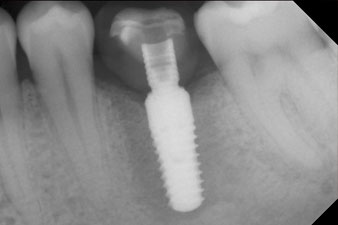

El torque en el momento de la carga mecánica fue de 43 Ncm. Asimismo, después de atornillar un poste de medición especial adaptado al sistema de implante (SmartPeg), el valor ISQ se determinó con la sonda del módulo Osstell ISQ de W&H.

Este módulo Osstell ISQ que se encuentra disponible como accesorio para la unidad Implantmed de W&H y se acopla al motor de implantes (véase figura 11). El valor ISQ adimensional fue de 64 justo en el momento de la inserción en la dirección bucovestibular y de 68 en la dirección mesiodistal (valor máximo = 100).